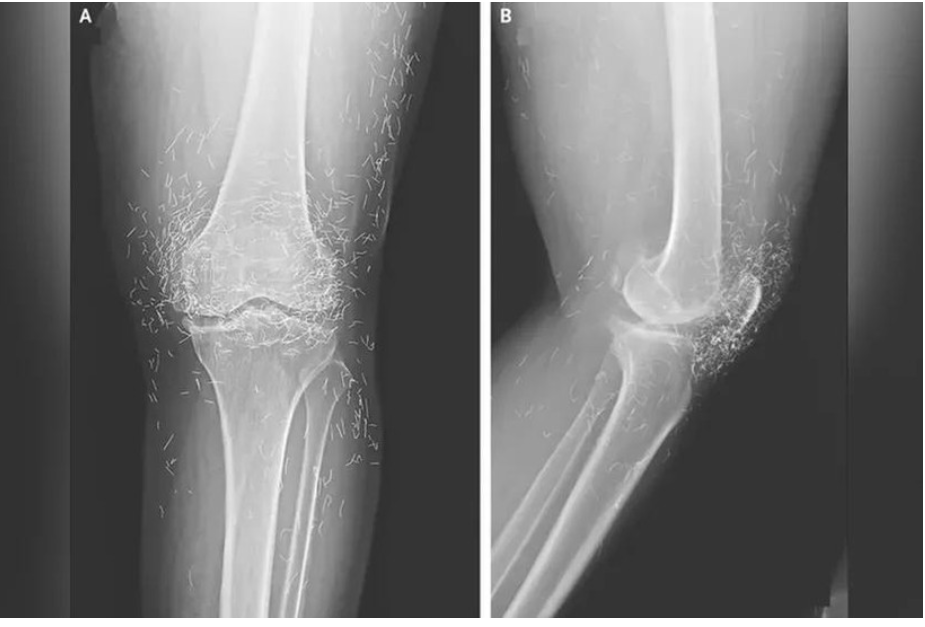

Ảnh chụp X-quang cho thấy hàng trăm sợi chỉ vàng trong đầu gối của nữ bệnh nhân. Ảnh: OddCentral.

Kết quả chụp X-quang cho thấy tình trạng dày và cứng bất thường ở phần xương chày trong, sự phát triển của gai xương quanh đầu gối – những triệu chứng điển hình của thoái hóa khớp – cùng với hàng trăm sợi chỉ vàng li ti được cấy vào các mô quanh khớp.

Các bác sĩ cảnh báo rằng châm cứu bằng chỉ vàng không hề có lợi ích y học nào được chứng minh, mà ngược lại tiềm ẩn nhiều nguy cơ. Những sợi chỉ nhỏ có thể gây u nang, di chuyển trong cơ thể và làm tổn thương mô xung quanh. Ngoài ra, chúng có thể khiến bệnh nhân không thể thực hiện các xét nghiệm MRI cứu mạng, do nguy cơ dịch chuyển kim loại gây tổn thương mạch máu.